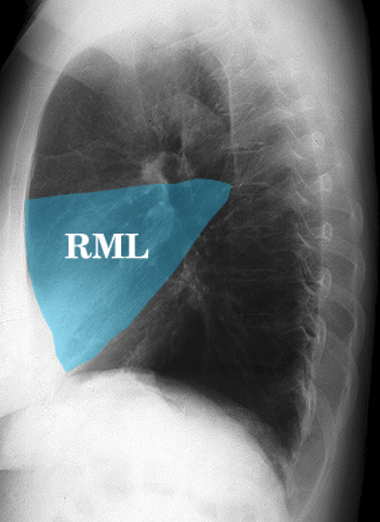

Which of the right lung lobes is typically smallest and triangular in shape?

A

Right Middle Lobe (RML)

Q

What is consolidation?

Inflammatory exudate of WBC, plasma, bacteria, and debris.

RML consolidation pictured.